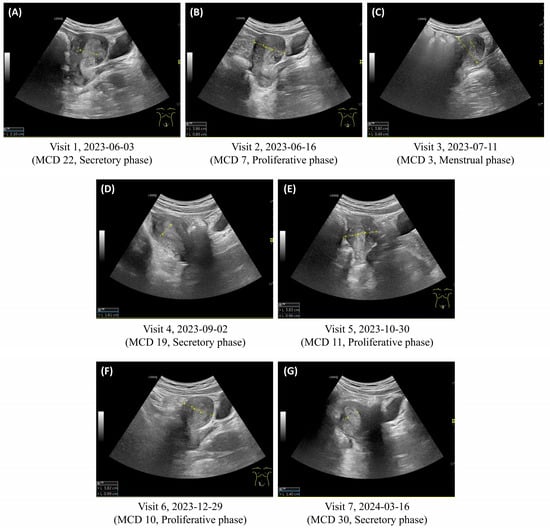

| Visits | Visit Date | Last Menstrual Period | MCD | Menstrual Pain (NRS) | Menstrual Volume * (Pads/Day) | Days of Menstrual Bleeding (Days) | Changes in Main Symptoms |

|---|---|---|---|---|---|---|---|

| 1 | 3 June 2023 | 13 May 2023 | 22 | 4 | 2–3 medium pads | 4 | Ovulation-related symptoms

Menstrual duration decreased from 6 to 4 days |

| 2 | 16 June 2023 | 10 June 2023 | 7 | 3 | 4–5 medium pads | 4 | Increased menstrual volume |

| 3 | 11 July 2023 | 9 July 2023 | 3 | 3 | 4–5 medium pads | 3 # | Decreased ovulation pain, headache (NRS 1–2) (discontinued analgesics) No headache or chills during menstruation |

| 4 | 2 September 2023 | 15 August 2023 | 19 | 3 | 4–5 large pads | 4 | Resolution of ovulation-related symptoms (pain, headache, body aches, nausea, bleeding) Restored to previous menstrual volume |

| 5 | 30 October 2023 | 20 October 2023 | 11 | 3 | 4–5 large pads | 6 | Restored to previous menstrual duration |

| 6 | 29 December 2023 | 20 December 2023 | 10 | 0–1 | 5–6 large pads | 6 | Almost no menstrual pain, normal menstrual volume |

| * Herbal medicine treatment completed | |||||||

| 7 | 16 March 2024 | 17 February 2024 | 30 | 0–1 | 4–5 large pads | 6 | Continued absence of ovulation-related symptoms, normal menstrual volume |